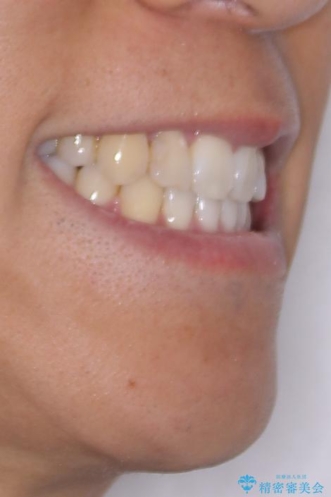

八重歯はきれいに整い、前歯もバランスよく収まり、横顔のラインも自然に改善されました。

治療後、患者様は「思い切り笑えるようになった」と大変喜んでくださいました。

治療後

• 八重歯と前歯のガタガタを抜歯矯正で治療|クリアブラケット使用例 治療後画像